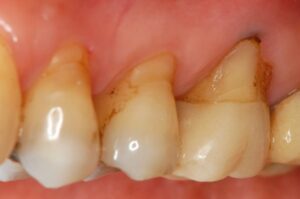

歯周病治療

歯周外科治療

Case Studies